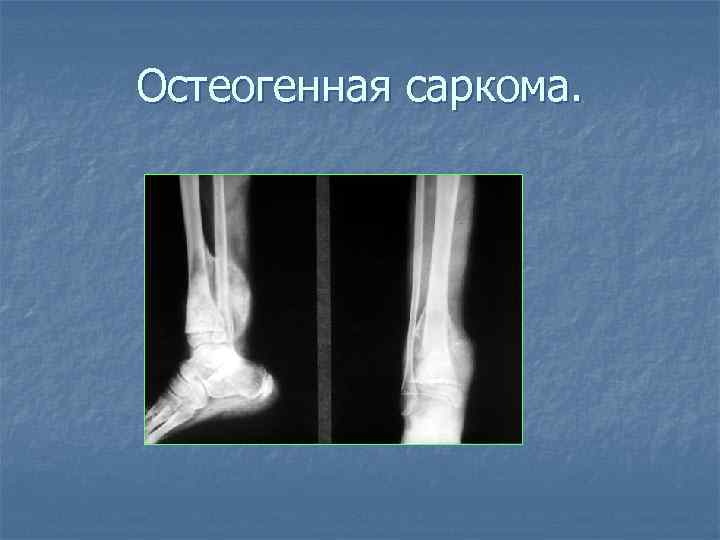

Остеогенная саркома.